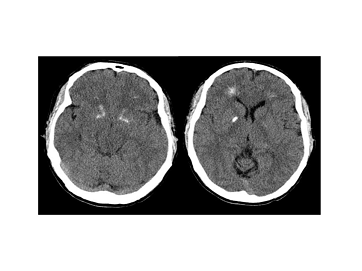

Рис. 9 Компьютерная томограмма мозга пациента с делецией

Рис. 10. Синдром Ди Джорджи